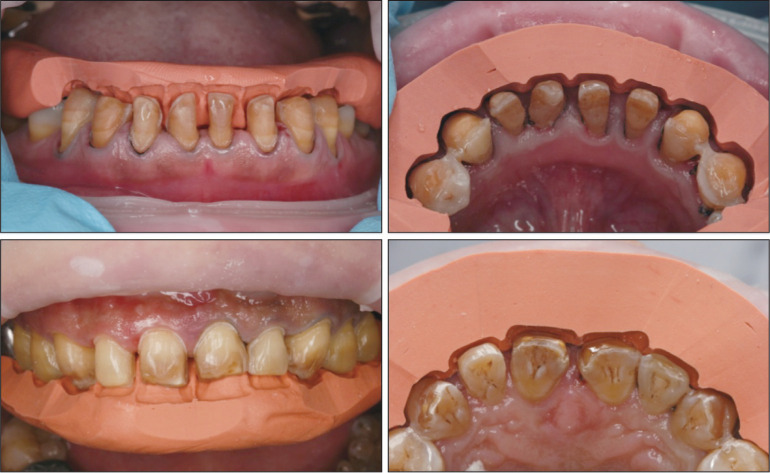

除了用硅橡胶进行导板制作外,自凝塑料或透明膜片等材料也可用于诊断饰面导板的制作,早在1984年就有医生使用并配合牙周探针检查预备量[20]。研究[21]显示,这类方法能有效保留釉质,提高粘接效果。这类引导方式使用最终修复体形态作为参考,不再只依赖术者的个体经验,相比经验类比引导方式更加准确(图3)。

图 3. 硅橡胶指示导板引导的牙体预备.

Fig 3 Tooth preparation guided by silicone index

左上:使用硅橡胶指示导板引导下颌前牙切端预备;右上:使用硅橡胶指示导板引导下颌前牙唇侧预备;左下:使用硅橡胶指示导板引导上颌前牙切端预备;右下:使用硅橡胶指示导板引导上颌前牙唇侧预备。

但这类方式也存在一定局限,主流的硅橡胶指示导板(silicon index)其预备量的控制仅为硅橡胶导板切割面,无法覆盖全部预备面,整体上看仍不精确;并且诊断饰面引导中使用的牙周探针测量的刻度为1 mm,小于1 mm数值依然是估算,与0.1~0.3 mm的百微米级牙体预备精度不通洽;另外面对过度扭转或倾斜的基牙时,诊断饰面制作困难或需要预先磨除多余部分才能进行诊断饰面的制作,故此类方法适合于难度较小的改形病例或二次修复。这类方法操作简便,效果相对可靠,适用于简单美学修复病例。